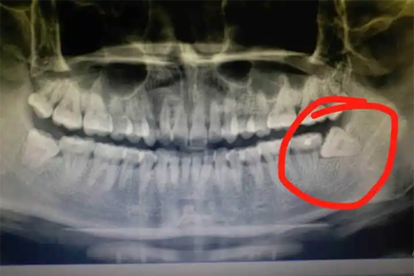

牙槽骨增生怎么去除

牙槽骨增生可通過手術(shù)切除、正畸治療、藥物治療等方式去除。牙槽骨增生可能與遺傳因素、慢性炎癥刺激、牙齒咬合異常等因素有關(guān),通常表現(xiàn)為局部骨質(zhì)隆起、牙齒排列不齊等癥狀。